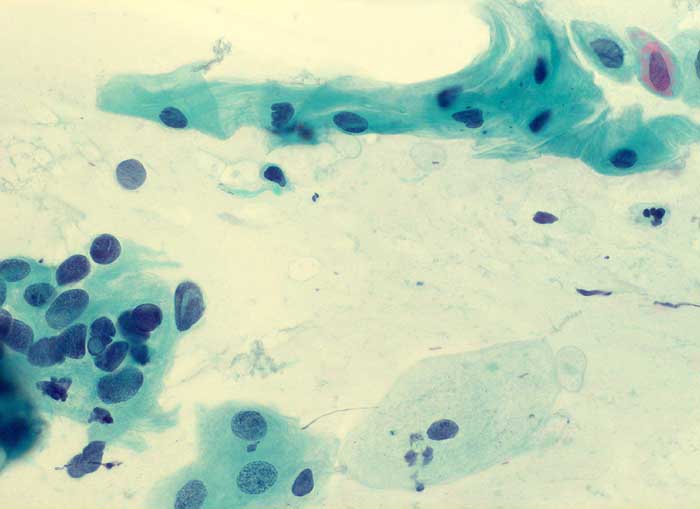

Nicht klassifizierbare Plattenepithelien (ASCUS)

Die Kategorie "atypical squamous cells of undetermined significance" der Bethesda Klassifikation umfasst entzündliche, reaktive und nicht klassifizierbare Plattenepithelveränderungen. Die Atypien übersteigen dabei das Mass gewöhnlicher reparativer Veränderungen. In den meisten Fällen sind reife Plattenepithelien betroffen. Nicht klassifizierbare Plattenepithelveränderungen können aber auch in metaplastischen oder atrophen Epithelien angetroffen werden. Die Diagnose ASCUS im atrophen Abstrich kann dann gestellt werden, wenn die Kerne mindestens zweimal so gross sind wie normal und eine deutliche Hyperchromasie zeigen, die Kernkontur bzw. Chromatinverteilung unregelmässig ist oder eine deutliche Pleomorphie in Form von Tadpole Zellen oder spindeligen Zellen vorhanden ist. In solchen Fällen kann nach einer kurzfristigen lokalen Östrogenbehandlung der Abstrich wiederholt werden. Gutartige atrophieassoziierte Veränderungen verschwinden unter Östrogentherapie. Signifikante präkanzeröse Läsionen persistieren hingegen und sind auf dem Hintergrund ausgereifter Zellen besser erkennbar.